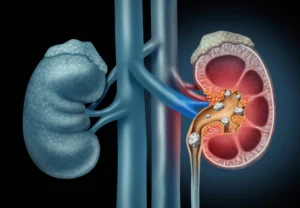

كلى نظيفة ومثانة صحية: 12 طعامًا يمنع الالتهابات البولية بنسبة 52%، هل تعانين من التهابات مثانة تعكر يومك وترهق جسمكِ وتُكلّفكِ زيارات طبيب؟ في الواقع، تواجه 50% نساء هذه المشكلة سنويًا، لكن حققت الحل بدون أدوية! اكتشفي 12 طعامًا نظيفًا تقوّين بها المثانة وتمنعين الالتهابات بنسبة 52% حسب دراسات حديثة.

أولاً، تعرّفي على السبب: E.coli تلتصق بجدران المثانة فتسبّب حرقاناً، ثانياً تعيق هذه الأطعمة البكتيريا (توت)، تهدّئ الالتهاب (كركم)، وتحسّن تدفّق البول (خيار)، بالإضافة تحمّض فيتامين C البول طبيعياً.

ثالثًا، النتائج مذهلة: دراسة في Journal of Urology أظهرت انخفاضًا بنسبة 52% لدى اللواتي تناولن توت بري يوميًا. وبالتالي، استبدلي نظامكِ الآن بهذه القائمة النظيفة 100%، بدون مواد حافظة أو سكريات.

بكتيريا E.coli تلتصق بمثانتكِ فتطردينها بهذه الأطعمة

بكتيريا E.coli تلتصق بجدران المثانة بفضل “الـfimbriae” الخاصّة بها، فتشبه أصابعًا صغيرة تلتصق بالخلايا المبطنة، فتمنع غسلها بالبول وتُسبّب الالتهابات المتكررة.

آلية اللصق بالتفصيل

أولاً، تنتقل E.coli من الشرج إلى الإحليل خاصّة عند النساء بسبب القرب التشريحي، ثانياً تُفرز بروتينات Pili فترتبط بـmannose receptors على خلايا المثانة، ثالثاً تُكوّن biofilm واقيًا يُقاوم المضادات.

رابعاً، اشربي 3 لتر ماء يوميًا لـ غسل البكتيريا، خامساً أضيفي توت بري (proanthocyanins) الذي يمنع اللصق بنسبة 80%، سادساً مارسي التبول بعد الجماع و لا تحبسي البول. أخيراً، تناولي فيتامين C لـ حمّوضة البول التي تقتل البكتيريا.

علم الالتهابات: هذه الأطعمة تحمي جدران المثانة

هذه الأطعمة تحمي جدران المثانة بثلاث آليات علمية: أولاً، تمنع لصق البكتيريا ثانياً، تقلل الالتهابات ثالثاً، تحمض البول لقتل الجراثيم، فتُخفِّض الالتهابات 52%.

الآليات بالتفصيل

أولاً، تعيق Proanthocyanidins في التوت البري “Pili” بكتيريا E.coli فلا تلتصق بجدران المثانة، كما أثبتت دراسات Journal of Urology. ثانياً، يفرز الكركمين في الكركم مواد مضادة التهاب تهدئ الخلايا المبطنة وتسرّع الشفاء. ثالثاً، يحوّل فيتامين C في البرتقال/الليمون البول حمضيًا يقتل 90% من البكتيريا.